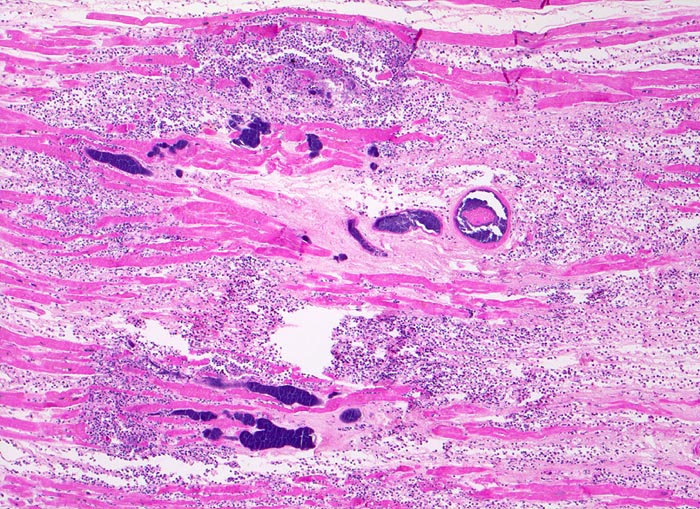

PathoPic – image database / PathoPic ID 3535 - septisch bakterielle Myokarditis (septikopyämische Myokarditis)

septisch bakterielle Myokarditis (septikopyämische Myokarditis)

Das nekrotische hypereosinophile Myokard wird infiltriert von neutrophilen Granulozyten. Die unregelmässig begrenzten blauen Flecken entsprechen Bakterienhaufen, welche teilweise intravaskulär lokalisiert sind.

Patient mit bakterieller Staphylokokken-Endokarditis der Aortenklappe bei bekanntem intravenösem Drogenabusus.

Dunkelblau in der HE Färbung sind: Bakterien, Kerne (hier der neutrophilen Granulozyten) und Kalk (nicht auf diesem Bild)